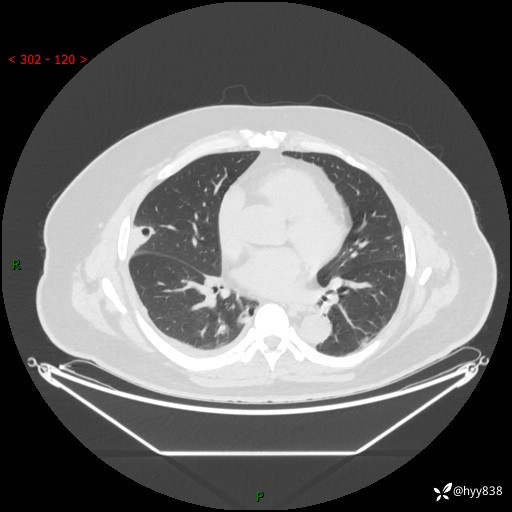

病例中年男性,发热来诊。典型?鉴别疾病谱有哪些,下一步---结果公布~

性别:男

年龄:48岁

简要病史:发热来诊(门诊病人)

胸部CT平扫